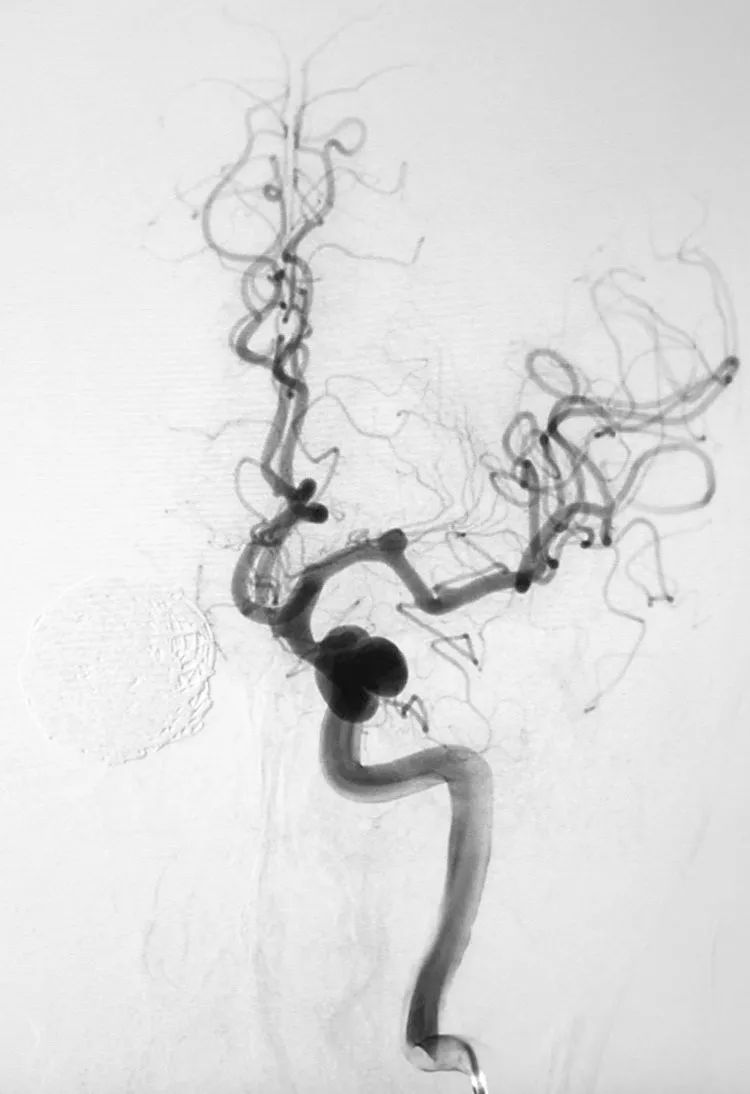

- 术前右颈内动脉造影显示右侧颈内动脉床突段巨大动脉瘤、床突上段中型动脉瘤。

- 巨大动脉瘤瘤体26.43 mm×26.77 mm,颈宽10.03 mm;中型动脉瘤瘤体8.26 mm×8.50 mm,颈宽5.75 mm。

术后右颈内动脉各角度造影显示大瘤部分栓塞,载瘤动脉畅通,希望通过一段时间的血流冲击使大瘤内的弹簧圈夯实,为二期支架导管的通过提供铺垫和支撑。

5F Navien中间导管置入右颈内动脉岩骨段,行右颈内动脉造影显示大瘤大部栓塞,瘤颈处开放。

术后右颈内动脉正侧位造影显示:右大脑前动脉不显影,考虑为血流动力学因素所致。